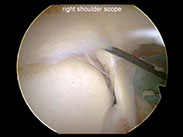

The biceps-labral complex is a significant pain generator in the shoulder. Traumatic or overuse injuries can cause a tear of the superior labrum – at the insertion of the biceps tendon. In addition, tendonitis of the biceps tendon is a common ailment in middle aged and older patients. There are many treatment options, both nonoperative as well as surgical.